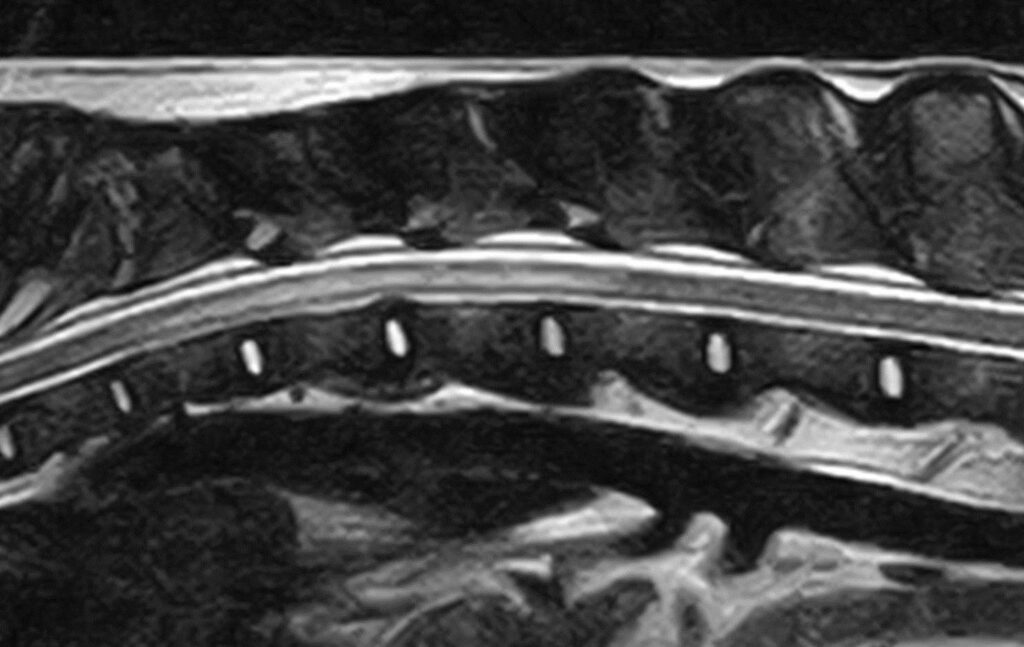

- An MRI scan

The results of these tests are usually normal in animals with ischaemic myelopathy although MRI can often show some compatible changes. Since you are relying on an absence of findings on imaging to make a diagnosis it is essential that the correct portion of the spinal cord is checked. Imaging studies may occasionally detect swelling of the spinal cord.